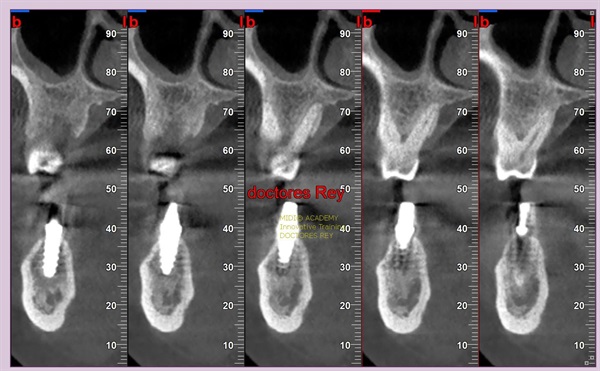

2-Implantes monobloque, en maxilar inferior. MIDI® TECHNIQUE® -US.

4x11,5. colocados con técnica ultarasónica MIDI®, hueso de calidad baja.